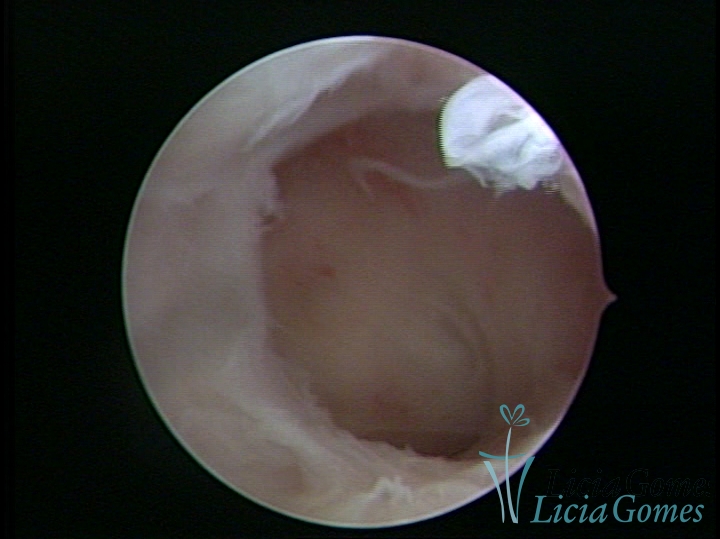

FIBROUS SYNECHIA

Uterine synechiae are scars (adherence) between the surface of the uterine walls, which may occur after the surgical procedure, uterine curettage, or after an inflammatory process in the uterine cavity (endometritis), which may lead to menstrual changes, infertility and obstetric complication such as abortion and premature birth.